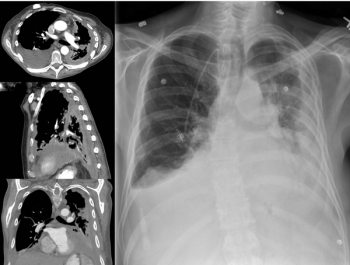

Investigators reported that, compared with chemotherapy, atezolizumab monotherapy was superior in overall survival and progression-free survival in patients with NSCLC.